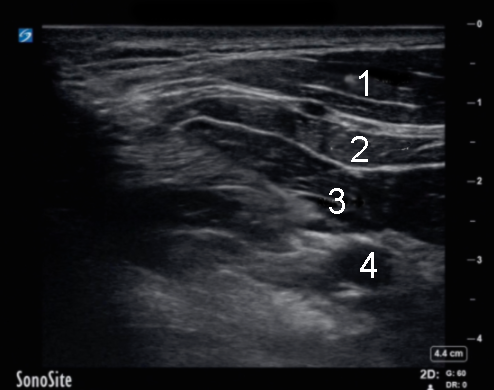

Bild: Infraklavikulärer Ultraschall

1. Musculus pectoralis major

2. Musculus pectoralis minor

3. Nadelspitze

4. Arterie